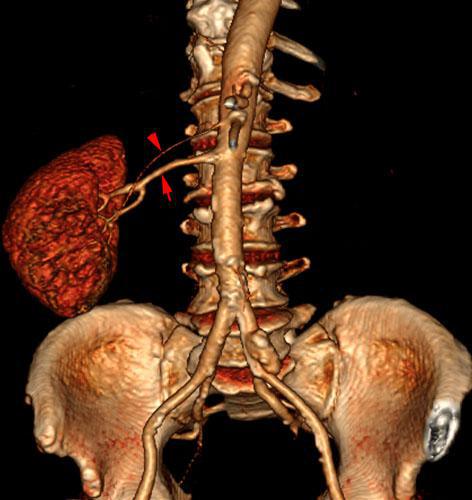

Riñón único pélvico